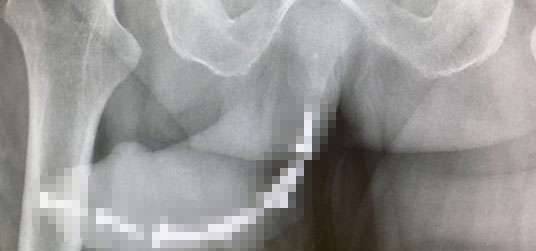

▼那名网友表示:「男子喝得大醉,感到不爽的女友就把12根螺丝插入男子的下体,快顶到尿道。」